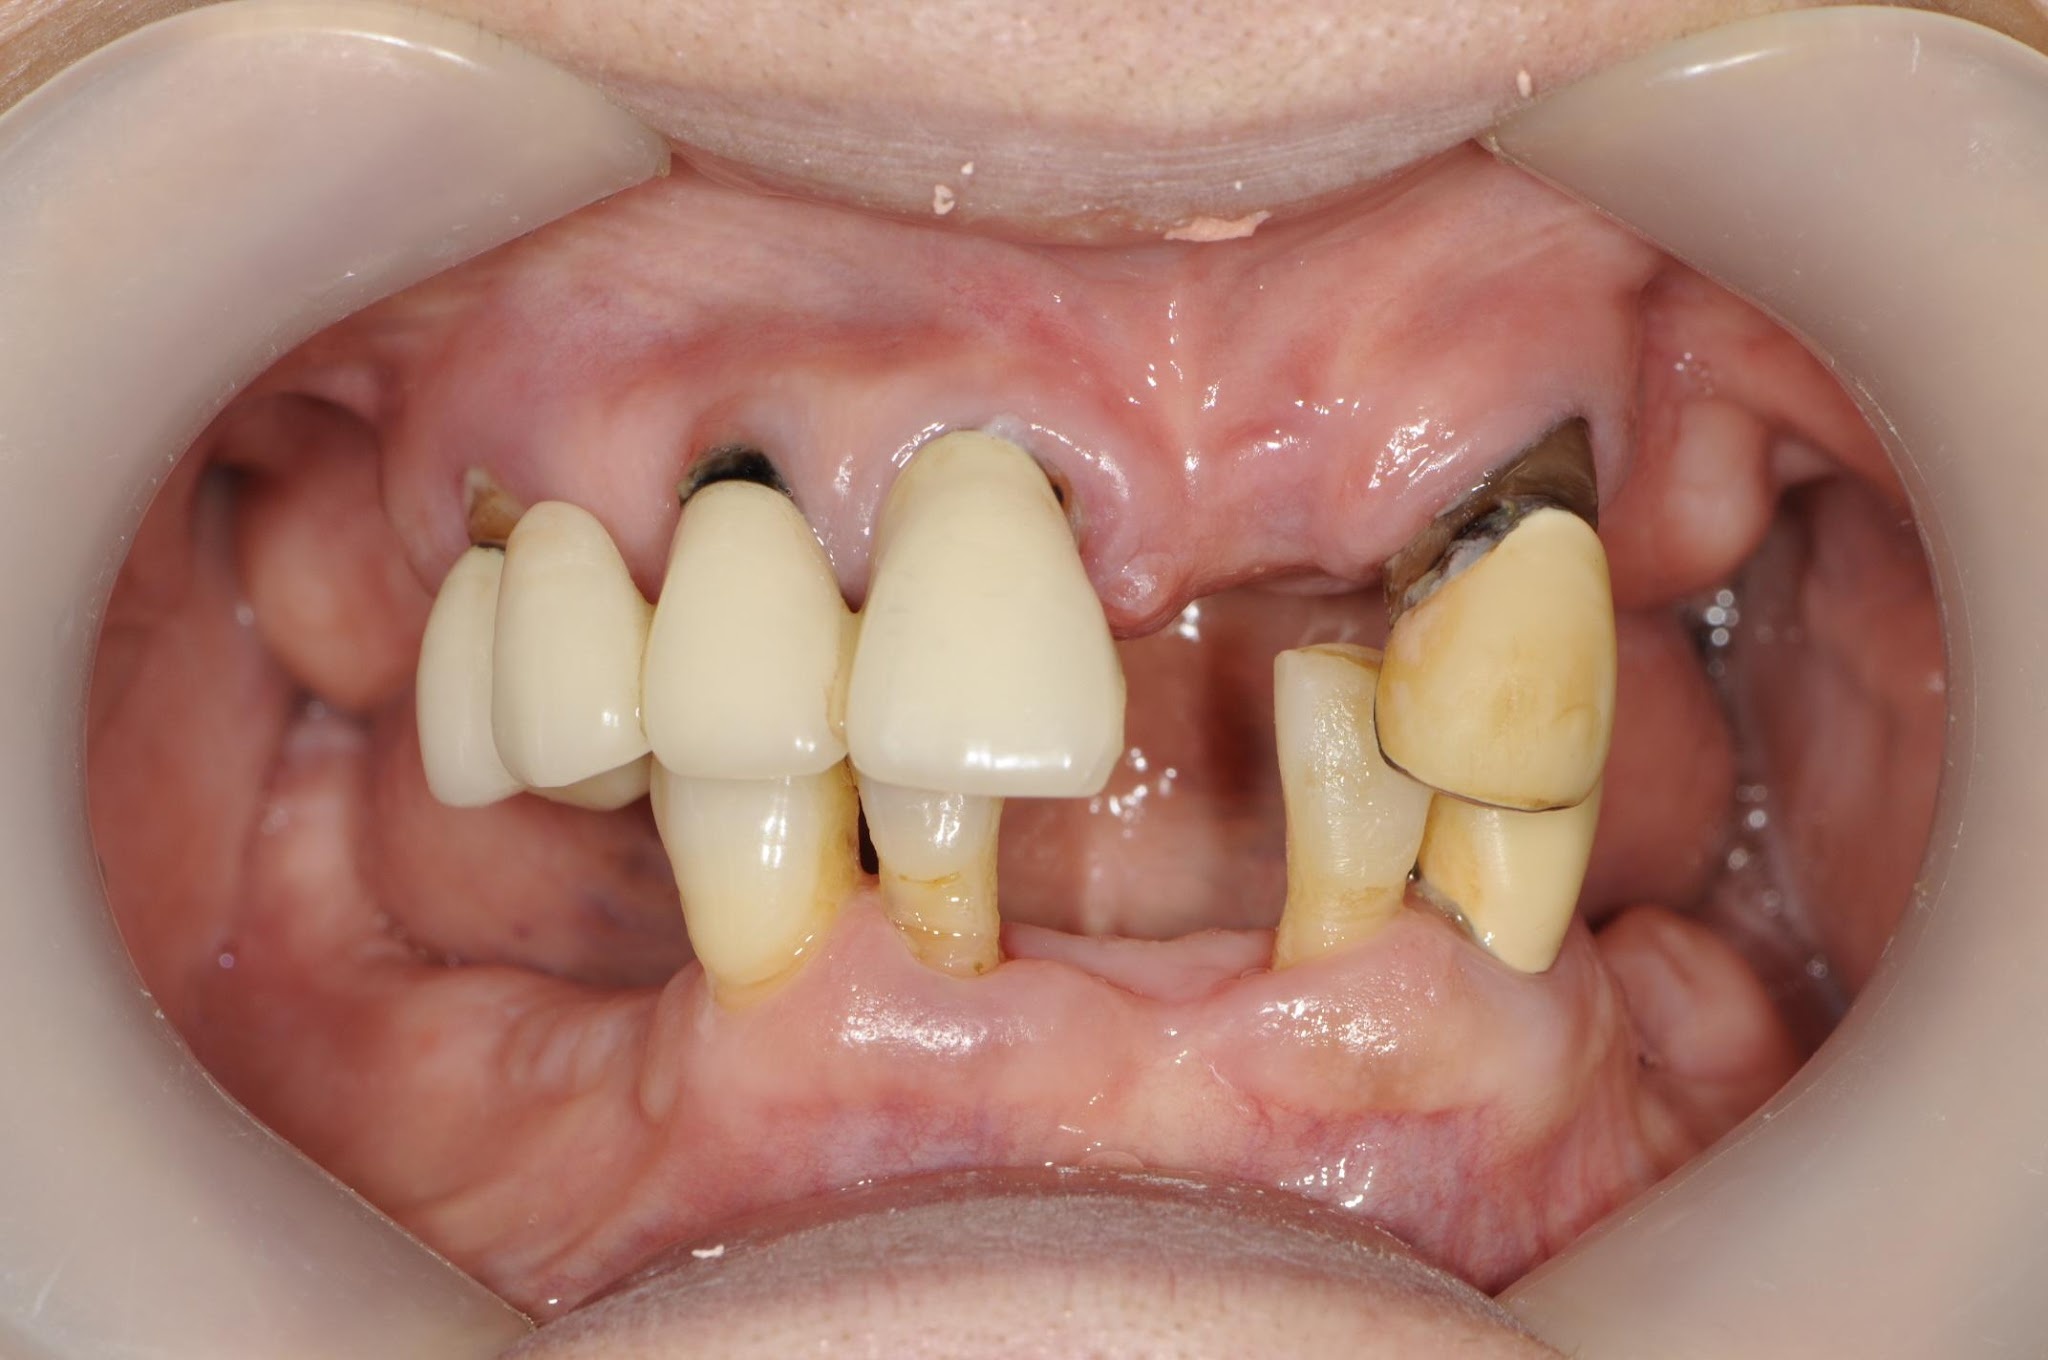

重度歯周炎による多数歯欠損に対する

インプラントおよびブリッジによる咬合再構成症例

主訴:歯がグラグラして気になる

診断:重度歯周炎による歯牙欠損および歯槽骨吸収

治療内容:

・インプラント埋入(8本)

・骨造成(必要部位)

・プロビジョナルによる歯肉形態および咬合調整

・上顎前歯部:セラミックブリッジによる補綴

・最終補綴:セラミッククラウン・ブリッジ

治療期間:約2年(通院回数:約24回)

費用:

インプラント:40万円 × 8本+インプラントブリッジポンティック=380万円

セラミックブリッジ:60万円 × 2=120万円

総額:約500万円(税込)

67歳からのインプラント治療で

76歳の今も快適に噛める状態を維持

この患者様は67歳の時に

「どうにかならないでしょうか」とご相談に来られました。

歯の欠損や不良補綴により、見た目だけでなく

しっかり噛めない状態が続いていました。

一度は入れ歯を使用されましたが、違和感が強く、

十分に機能しない状態でした。

そこでインプラント治療による

口腔全体の再設計を行いました。

ワックスアップにより最終形態を設計し、

噛み合わせや力のコントロールを含めて治療しています。

現在は76歳になられますが、問題なく噛める状態を維持し、

口腔内も良好な状態を保っています。

年齢に関わらず、適切な診断と設計によって

生活の質を大きく改善できる可能性があります。